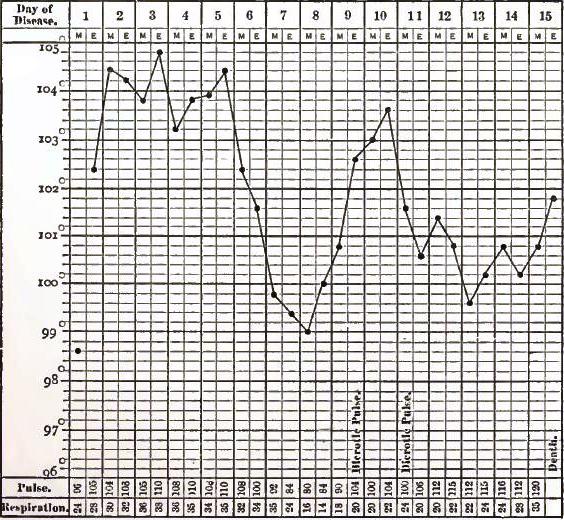

| 12. | CHART OF TYPICAL RANGE OF TEMPERATURE IN TYPHOID FEVER, AFTER WUNDERLICH |

Of all these manifold evidences of fever, the elevation of temperature is the one whose cause, range, and results have been most carefully and critically investigated. No record of a case in which fever is present is regarded as complete without the chart of the daily variations in temperature, respiration, and circulation. The practical value of such records is thus admitted, and in the experiments relating to the origin of animal heat the observations of temperature are as essential as the chemical analyses, each of which supplements the other.